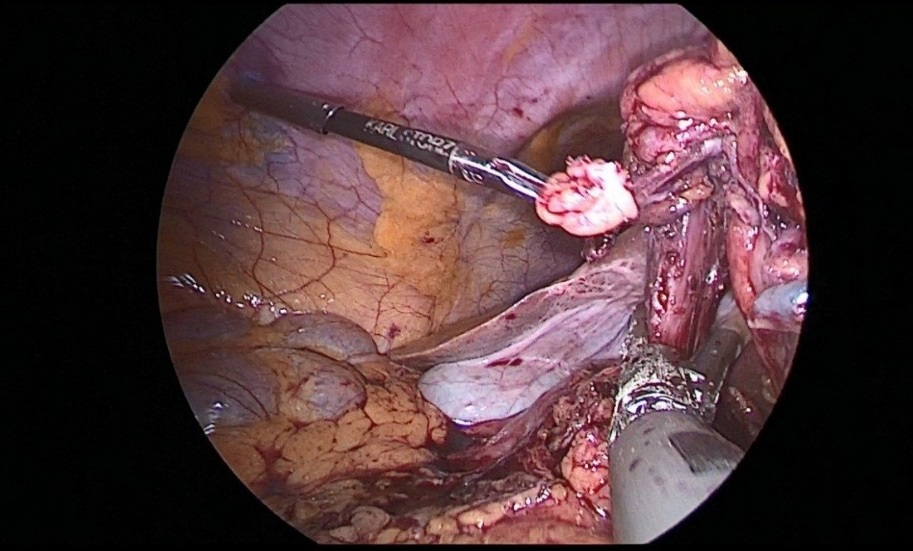

Further, 30 cm away from the ligament of Treitz, the jejunum was transected to apply esophagojejunal anastomosis, then the abdominal part of the esophagus was mobilized, with a pursestring suture with a Vicryl 2.0 thread on the adventitia of the esophagus (Figure 11a,b).

This completed the laparoscopic stage of the operation. Next, a minilaparotomy up to 6 cm long was performed along the white line of the abdomen, retreating 5 cm below the xiphoid process. The stomach was transected at the level of the cardioesophageal fold, after which the jejunum was brought to the abdominal esophagus through the mesocolon window. Then, a circular stapler was inserted through the free edge of the transected jejunum, and a hole was made at a distance of 10 cm from the resected edge along the antimesenteric, into which a circular stapler was inserted and end-to-side esophagojejunostomy was applied (Figure 12).

Figure 12: End-to-side esophagojejunostomy was applied.